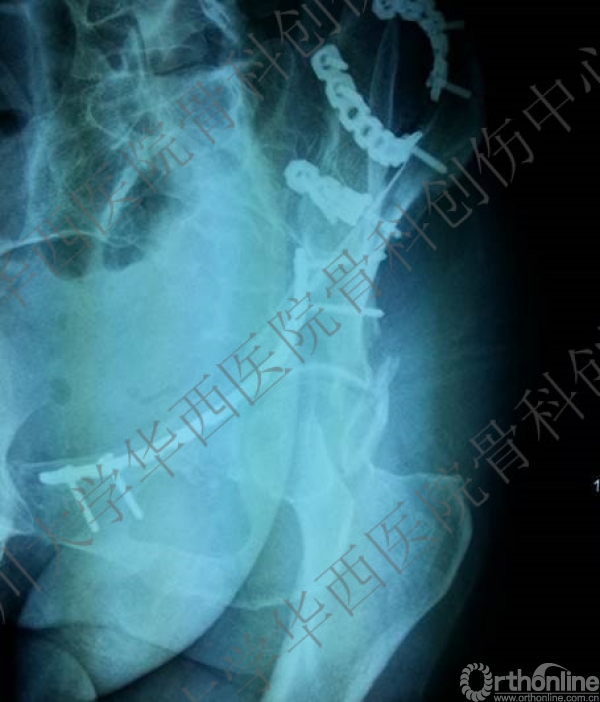

术后CT

术后冠状位及横切面CT扫描,负重区解剖复位

术后CT也证实骨盆形态正常。